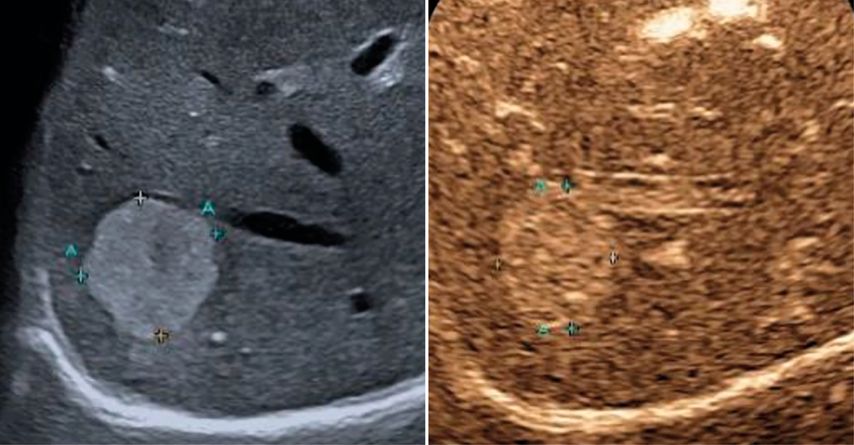

In der früharteriellen Phase zeigen benigne Läsionen wie Hämangiome typische Füllungsmuster ohne «wash-out» in der Portal- oder Spätphase (Abb.1). Maligne Läsionen hingegen weisen meist ein rasches «wash-out» auf und stellen sich in der Spätphase hypokontrastiert dar (Abb.2).3,4

Abb. 1: Typisches Kontrastmittelverhalten eines Hämangioms in der Spätphase mit Hyperenhancement gegenüber dem umgebenden Leberparenchym (rechts)

Abb. 2: Darstellung einer hochgradig Metastasen-suspekten Raumforderung bei Mamma-Neoplasie im linken Leberlappen im B-Bild-Modus (rechts) sowie in der Spätphase nach Gabe von 1,6 ml SonoVue® mit Darstellung eines deutlichen «Wash-out»-Phänomens in der Spätphase 4 Minuten nach Injektion des Kontrastmittels (links)